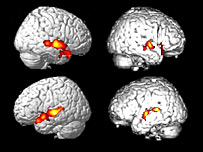

Beyin filmleri

Farklı faaliyetler beynin farklı bölgelerini harekete geçiriyor

Beyin filmleri, beynin konuşmaya dair bölgelerinin sağlıklı deneklerle aynı şekilde aydınlandığını gösterdi.

İkinci denemede bu kez hastadan tenis oynadığını ve evde yürüdüğünü düşünmesi istendi.

Bu sırada da beynin uzuvların hareketinden sorumlu motor kontrol bölümleri aydınlandı.